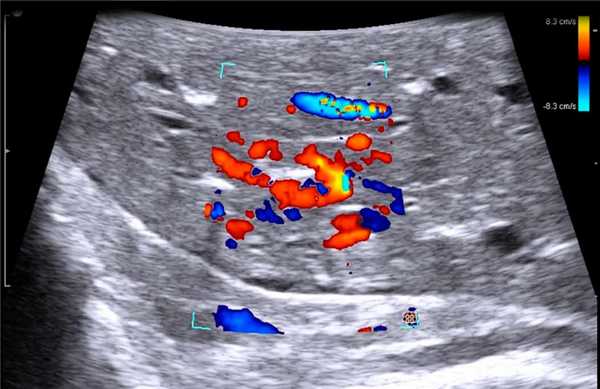

В случае выявления образований в печени и измененных забрюшинных лимфатических узлов (при необходимости) выполняли пункционно-аспирационную биопсию. При этом образование, эхографически подозрительное на метастатический узел, располагалось по центру сканирующей поверхности датчика и тем самым по центру монитора. При исследовании обязательно использовали методику допплерографии для выбора участков с наименьшим кровоснабжением. Эта же методика позволяла визуализировать кровеносные сосуды над узловым образованием и избежать их повреждения. После выполнения указанных моментов выполняли непосредственно пункцию.

Клинический пример N2. Пациентка Р. находилась на лечении в ГУРОНЦ РАМН. При прохождении обследования был установлен диагноз рак толстой кишки. По данным ультразвуковой компьютерной томографии на фоне выраженной диффузной неоднородности паренхимы печени очаговые образования не определялись. При проведении ангиографии и компьютерной томографии так же убедительных данных за наличие метастазов в печень получено не было. При интраоперационном ультразвуковом исследовании были выявлены два очага, характерными особенностями которых являлись малые размеры (0,2 - 0,4 см), а так же нечеткость контуров и изоэхогенность структуры (рис. 1 а,б).

Рис. 1. Метастатические очаги (стрелки) в печени при интраоперационной ультразвуковой томографии.